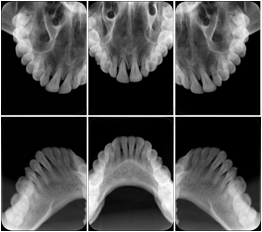

- OO-1. Intra-oral Full Mouth Series Structured Display